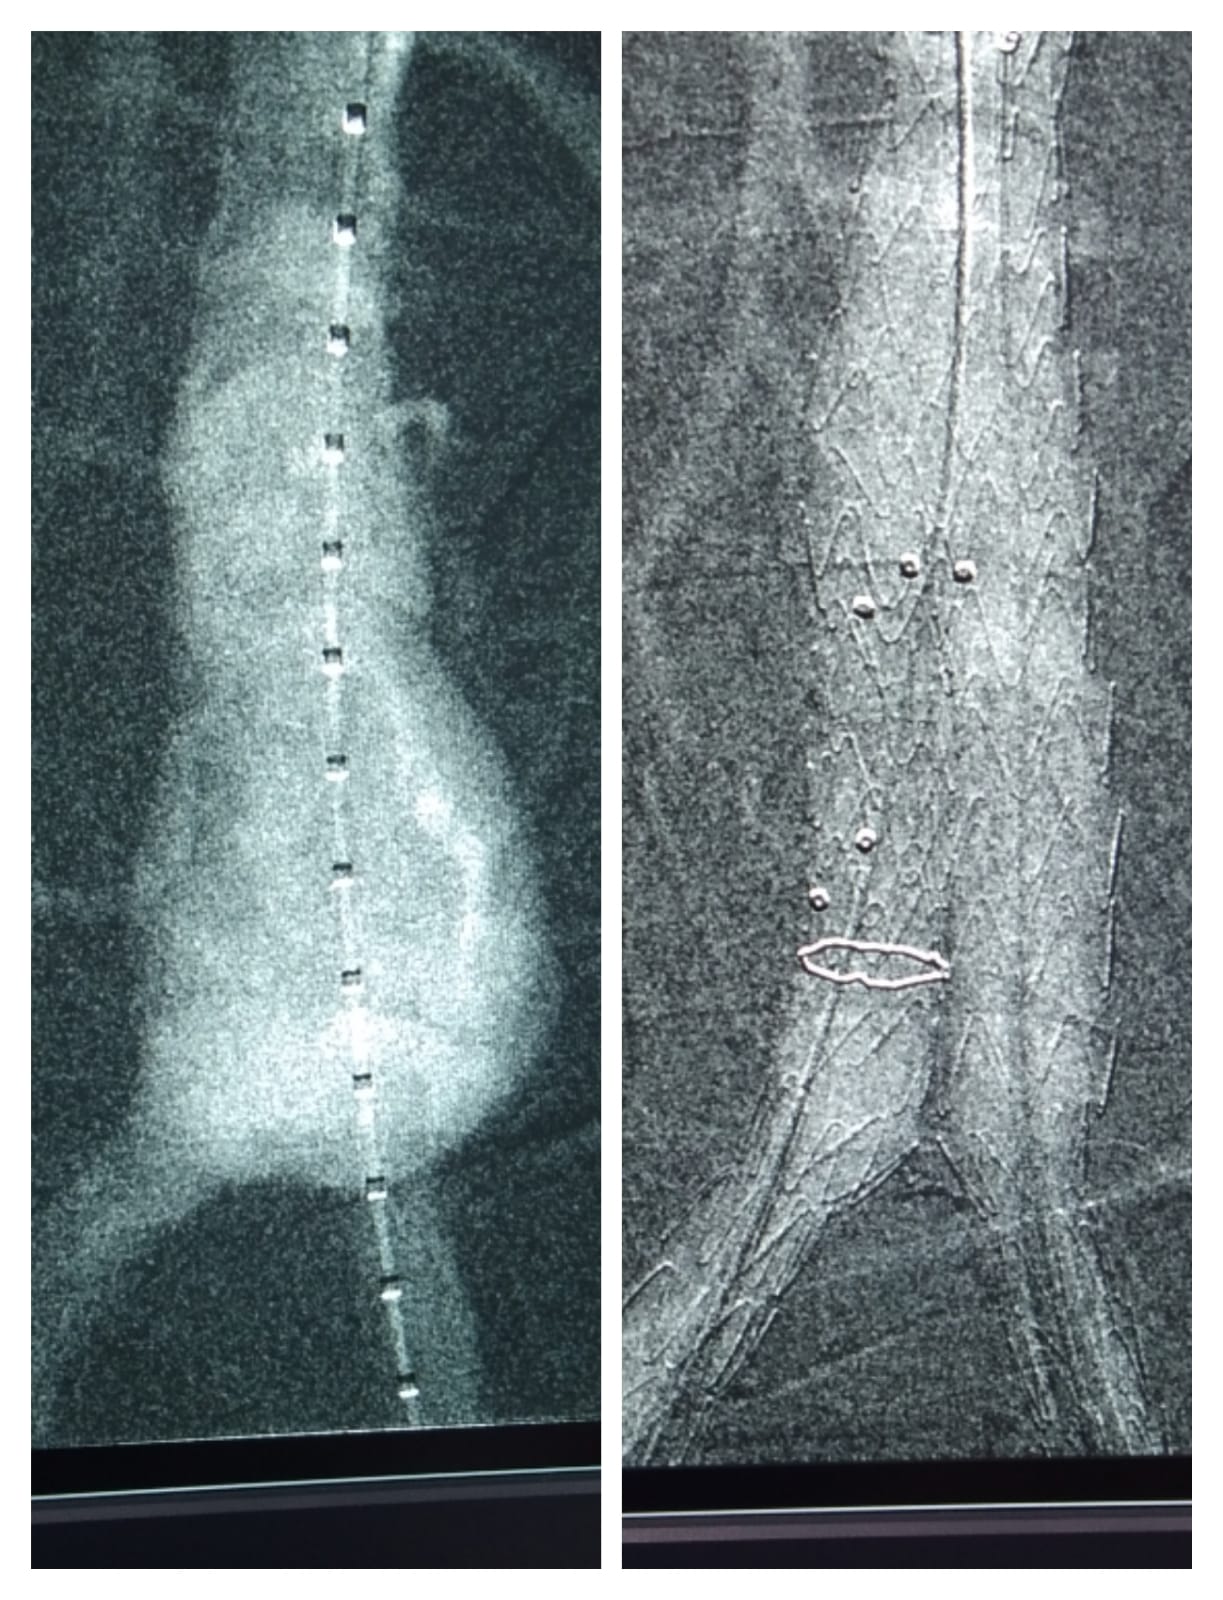

Dialysis AV Fistula procedure - Pre Procedure & Post Procedure

Uterine Artery Embolization